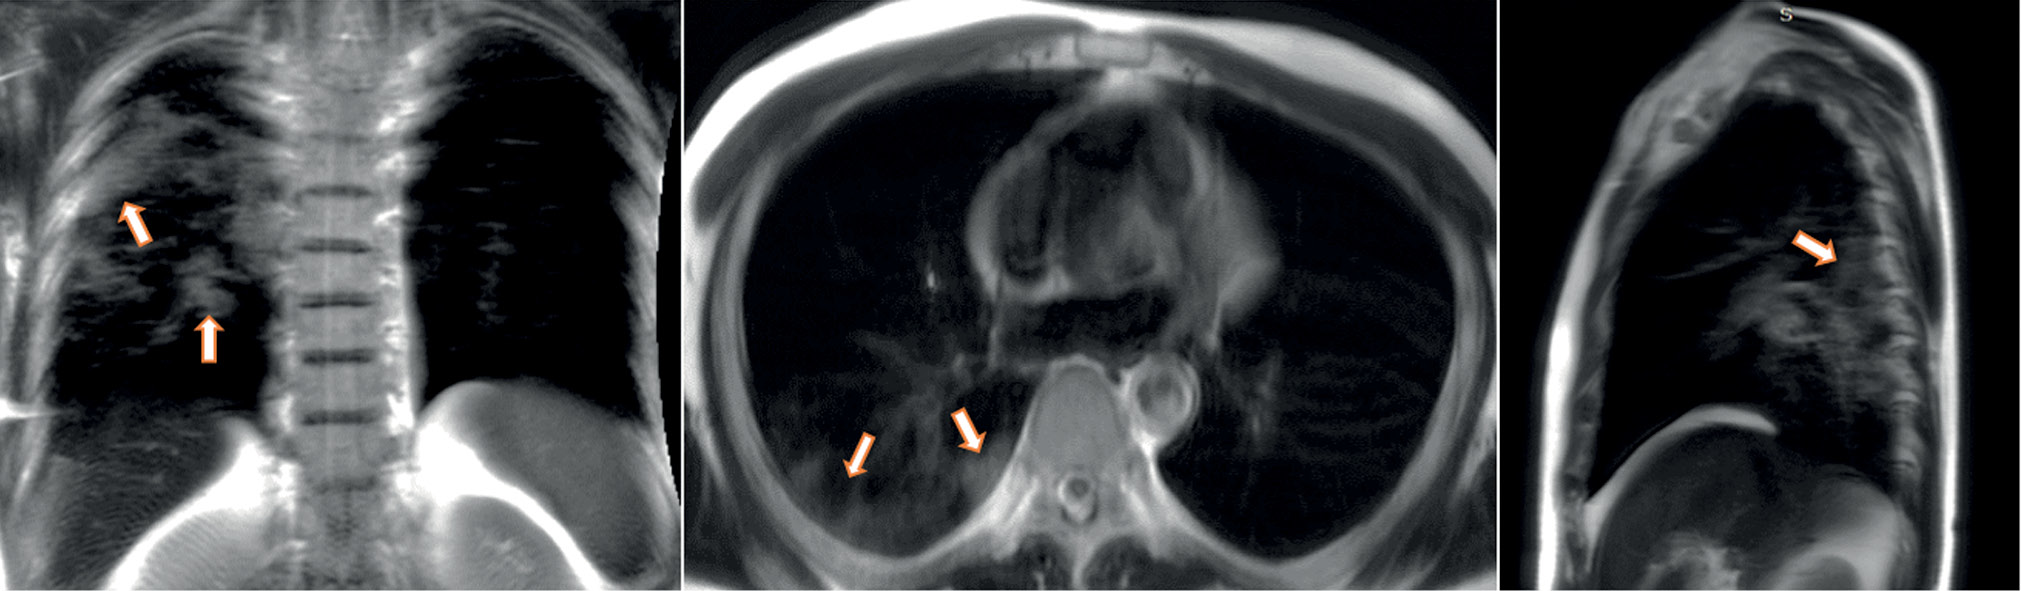

A patient (female, 45 years old) presented to the clinic on the fifth day after the onset of dry cough and mild fever up to 37.5°С. Dynamic lung MRI in the coronal plane (Fig. 1) showed an area of hyperintense signal in the lower lobe of the right lung (S9–S10), interpreted as an area of central induration (more intense signal) with a surrounding “cloudy sky” (less intense signal) during inhalation. A hyperintense signal was found in the corresponding area in the axial and sagittal planes, indicating consolidation with a “cloudy sky” along the edge of the area. At the end of exhalation, increased signal intensity was observed in the described area in the coronal plane (Fig. 2) with decreased visual size of the affected areas due to lung tissue contraction. During exhalation, no changes in signal intensity were observed in the axial and sagittal planes.

Figure 1. Dynamic magnetic resonance imaging of the lungs during inhalation in the coronal, axial, and sagittal planes. In the axial and sagittal planes, arrows point to areas of compaction. In the coronal plane, the arrow points to a “cloudy sky” (S9–S10).